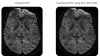

DTI denoising

Based on image redundancy and/or sparsity, the proposed filters provide efficient denoising while preserving fine structures.